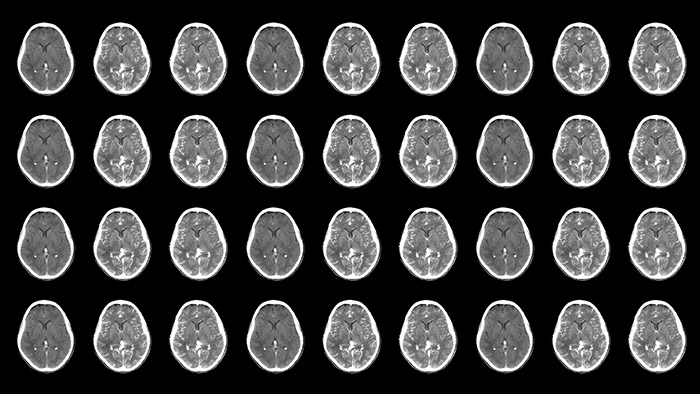

Neurovascular decisions are based on what you see, so see more

Neurovascular care encompasses a remarkable range in approaches to treatment. On one hand, stroke cases are acute and always require immediate treatment for the greatest chance of improving the patient’s quality of life. On the other hand, planned procedures such as complex treatments for aneurysms and arteriovenous malformations (AVMs) need to be meticulously designed and executed to minimize the inherent risk. Neuro suite with SmartCT makes advanced 3D imaging accessible, offering superior workflow with excellent image quality at low dose. Innovative stroke tools, thoughtful collaboration with partners and 24/7 support help you deliver superior neurovascular care.

Neuro suite offers a flexible portfolio of sophisticated 3D imaging, integrated imaging, integrated technologies, neuro accessories and valued-added services that puts you on top of things, whether treating an acute stroke patient or working precisely through a complex AVM. This allows you to act with confidence, supported by high levels of procedural efficiency and standardization to help redefine outcomes for your patients and provide a positive workflow experience for staff.

Improved neuro CT-like cone beam CT images (CBCT) to identify ischemic changes in the Angio suite. The advanced protocol with dual-axis acquisition trajectory and improved reconstruction software results in improved image appearance, compared to conventional CBCT acquisition techniques.